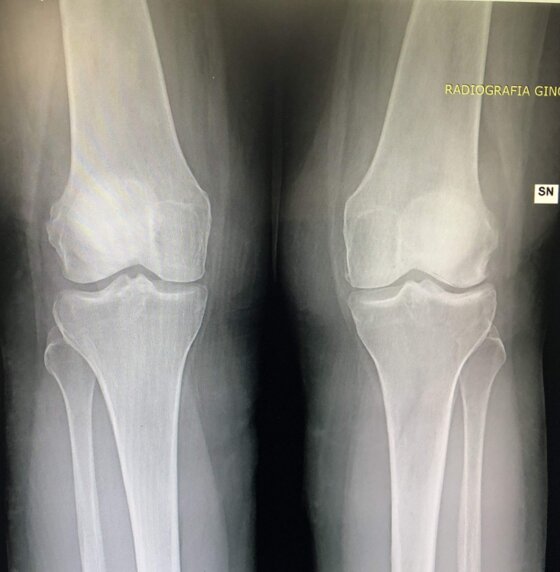

Radiografie post-operatorie in AP di interventi chirurgici di artroprotesi cementate di ginocchio eseguiti in due pz con allergia ai metalli (nichel). Sono state utilizzate due protesi di due arche differenti, entrambe anallergiche (nichel-free) con conservazione del LCP (CR)